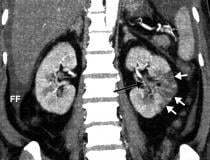

This photo gallery shows the variety of radiological presentations of COVID-19 (SARS-CoV-2) in medical imaging, including computed tomography (CT), radiograph X-rays, ultrasound, echocardiograms and magnetic resonance imaging (MRI). The radiology images show examples of typical COVID pneumonia in the lungs and the numerous complications the virus causes in the body in multiple organs, including the brain, kidneys, heart, abdomen and vascular system.